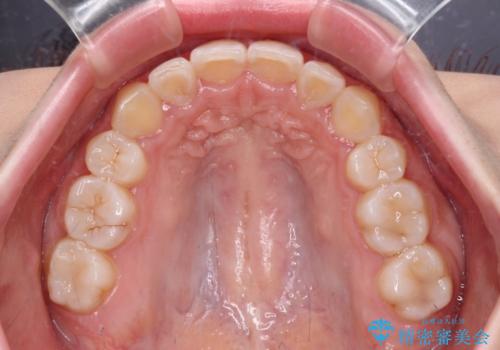

- 上顎の八重歯と、上下前歯のデコボコを気にして来院された患者様です。

奥歯の咬み合わせを見ると、上顎臼歯が下顎に対して前方にあり、叢生改善により口元が突出する顔貌ではなかったため、上顎左右第一小臼歯2本を抜歯し、ワイヤー装置にて矯正治療を行うこととしました。

前歯部のデコボコがなくなったため、歯磨きしやすくなり、非常に清潔な状態になりました。